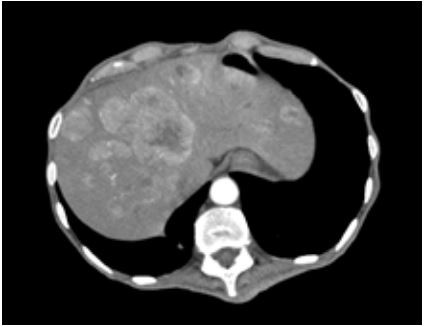

Paciente masculino, 64 anos, veio encaminhado para avaliação de quadro de fraqueza, perda de peso (23Kgs nos últimos seis meses) e evacuações diarreicas cerca de 20x ao dia, sem muco, sangue ou pus. Em uso domiciliar de glicazida 60mg ao dia devido a diagnóstico recente de diabetes. Ao exame físico emagrecido, com índice de massa corpórea de 15 Kg/m² , com placas orais sugestivas de monilíase, erosões crostosas e placas amarronzadas no dorso e membros, com fígado endurecido, palpável a 4 cm do rebordo costal direito. Exames laboratoriais evidenciaram anemia normocítica e normocromica, discreta plaquetose, hipoalbuminemia, com sorologias para hepatites virais e HIV negativas. Exame de fezes com gap osmolar fecal de 5,02 Osm / kg H2O, ausência de hemácias, leucócitos, leveduras, ácidos graxos, helmintos ou protozoários. Tomografia contrastada de abdome mostrou lesão sólida com captação de contraste de 2,4cm em corpo / cauda de pâncreas e múltiplas lesões nodulares hepáticas, estas evidenciadas na figura a seguir: